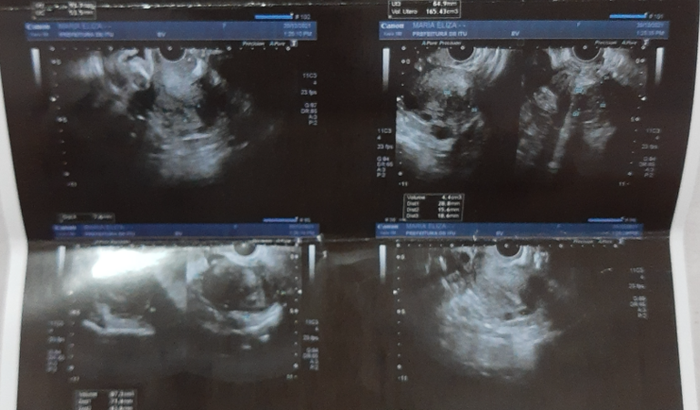

Me chamo Maria Eliza, tenho 34 anos, e descobri que tenho vários miomas no útero á 7 anos atrás, eu estava na fila do SUS, e sempre me davam desculpas dizendo que não havia chego minha vez, nesse período eu trabalhei em um lugar que não havia convênio na época o problema(mioma no útero) não era muito grave, porque ainda estava pequeno e convênio particular muito caro, eu resolvi esperar chegar minha vez “o mioma” sim, era 1 só. Porém com o passar dos anos apareceu vários outros e o 1° que apareceu na época esta enorme e ele mexe muito. Ano passado como eu vi que estava demorando mais que o normal e eu fui até o posto de saúde, saber o porquê de tantos anos essa demora e fui ver novamente quando seria minha vez sem respostas eu resolvi marcar novamente ginecologista e marquei uma consulta novamente, quando chegou o dia da consulta a médica que me atendeu pela primeira vez e me explicou o que houve. Desde que havia fechado a antiga santa casa de Itu, foi perdido o sistema de todos os pacientes que estavam na fila de espera de cirurgias e eu teria que começar do 0 tudo de novo. Então a médica pediu tudo com urgência meus exames e assim foi feito no decorrer do ano, estou passando uma fase difícil eu necessito retirá-los, pois fazem 5 meses que estou menstruando direto, o caso agravou e estou gastando horrores com higiene pessoal. Estou fazendo essa vaquinha porque a cirurgia é muito caro no valor de R$13.000,00 e estou na fila de espera novamente do SUS, mas está demorando muito mesmo estando grave a situação. Se puderem me ajudar doando o valor que puderem eu agradeço, só Deus pra pagar essa ajuda. Obrigada pela atenção, Deus abençoe a cada um